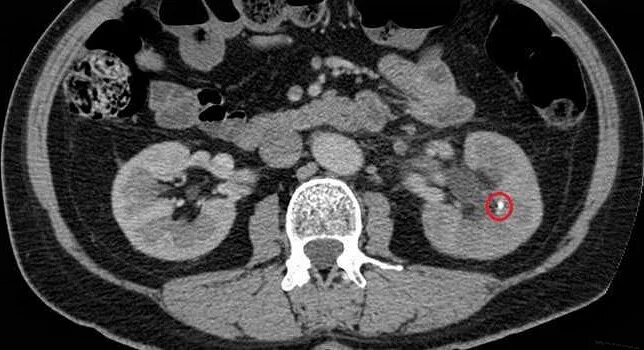

Микролитиаз почек узи. конкремент левой почки 3 мм узи. узи мочеточника камень 3 мм. камни в почках на узи.

Кальцинаты сосочков пирамид почек. кальцинаты пирамидок почек.